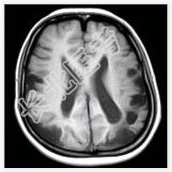

- [材料题] 女性,22岁。癫痫发作及智力异常。MRI显示见下图。